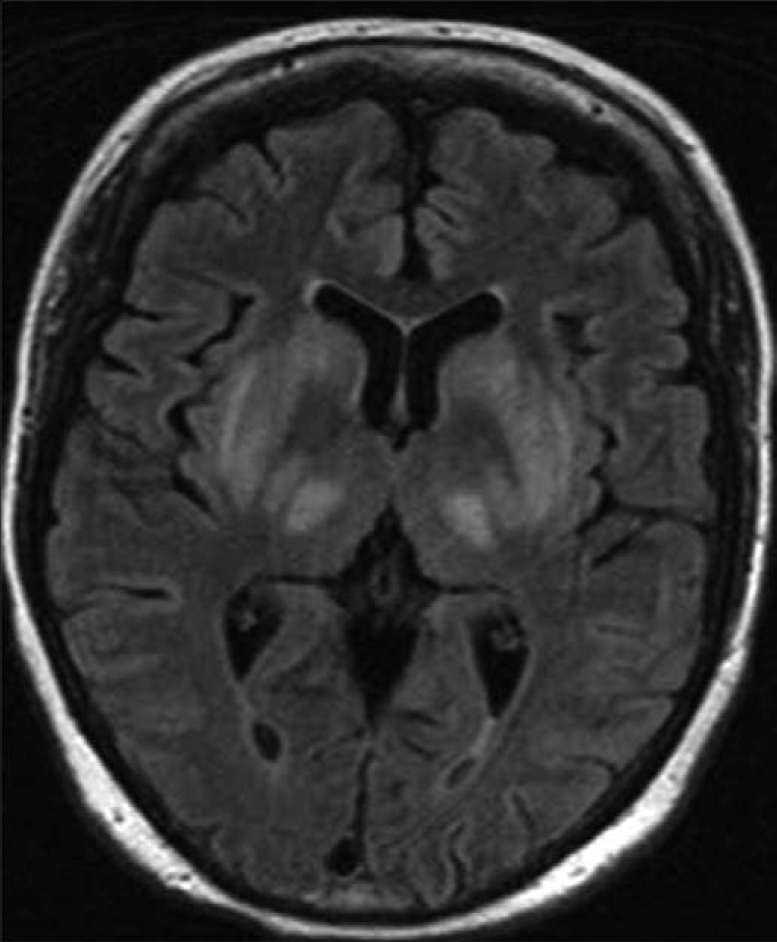

脑血管病包括哪些疾病?

脑缺血一过性发作,24小时内可完全恢复正常,但反复发作者有可能进展为脑梗塞3 其他缺血性脑血管病 包括由脑动脉硬化或各种脑动脉炎脑动脉缺血综合征颅内静脉窦或静脉血栓等引起的脑血管病以上各类脑血管病的临床表现治疗原则和...